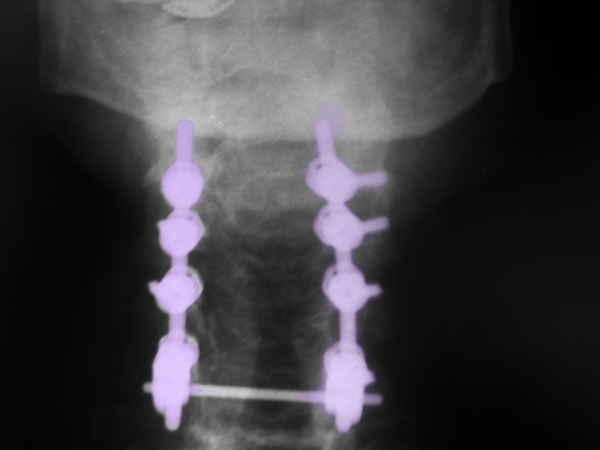

Περιγραφή Η οπίσθια αυχενική σπονδυλοδεσία πραγματοποιείται υπό γενική αναισθησία και με τον ασθενή σε πρηνή ή καθιστή θέση. Η τομή του δέρματος γίνεται στο μέσο του αυχένα και κατόπιν παρασκευάζονται τα οπίσθια στοιχεία της σπονδυλικής στήλης. Η σταθεροποίηση του αυχένα γίνεται με τη βοήθεια συστήματος με βίδες και ράβδους. Οι βίδες τοποθετούνται ή στα πλάγια ογκώματα ή στους αυχένες των αυχενικών σπονδύλων που πρόκειται να συνδεθούν, υπό ακτινοσκόπηση, και οι κεφαλές τους συνδέονται με ράβδους ενώνοντας με αυτό τον τρόπο τους σπονδύλους που χρήζουν σταθεροποίησης. Η τοποθέτηση των βιδών ακολουθείται, όταν αυτό απαιτείται, από πεταλεκτομή. Η ινιοαυχενική σπονδυλοδεσία διαφέρει στο ότι στη σπονδυλοδεσία συμπεριλαμβάνεται και το ινιακό οστό, στο οποίο επίσης τοποθετούνται βίδες και αυτές ενώνονται μέσω ράβδων στις βίδες των αυχενικών σπονδύλων σταθεροποιώντας έτσι και την ινιοαυχενική άρθρωση. |

Οπίσθια αυχενική πεταλεκτομή και σπονδυλοδεσία Α4-Α7. |